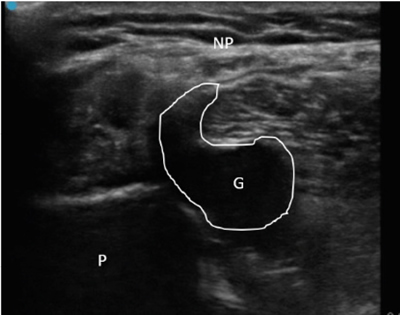

Neuropatía peronea secundaria a ganglión extraneural: revisión de literatura y propuesta de tratamiento. Caso no positivo

Peroneal neuropathy caused by an extraneural ganglion: literary review and treatment proposal. A non-positive case

Este artículo presenta el caso de un paciente de 69 años con una neuropatía compresiva peronea secundaria a un ganglión, inicialmente interpretada como una radiculopatía L5. Este incorrecto enfoque supuso la sobremedicación del paciente, un mal control algésico, la realización de una discectomía L4-L5 innecesaria y una pobre evolución neurológica.

Un enfoque diagnóstico correcto y un abordaje terapéutico precoz habrían supuesto una mayor mejoría clínica e incluso una recuperación neurológica completa del paciente. Por ello, este caso sirve para resaltar: a) el valor de la ecografía en neuropatías periféricas como herramienta diagnóstica y pronóstica y el de la ecografía en gangliones como arma diagnóstico-terapéutica; b) el uso de las pruebas diagnósticas como apoyo a una exploración física exhaustiva, y no como diagnóstico en sí mismas, y c) la importancia de la publicación de casos no positivos para optimizar recursos, evitar repetir errores, reducir el sesgo de publicación y facilitar el inicio de proyectos de investigación.

Figura 1